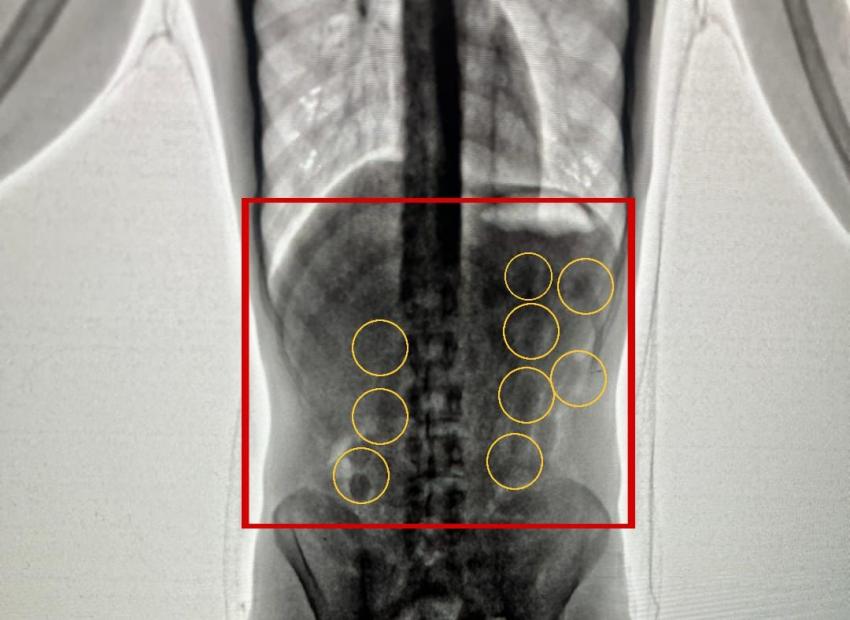

وبعد تفتيشهما والكشف عليهما بواسطة الاجهزة اللازمة اكتُشف وجود كميات من المواد المخدرة داخل أحشائهما ، وجرى إخراج هذه المواد بالطرق الطبية، وقُدرت ب 2 كغم من مادة الكوكايين المخدرة .